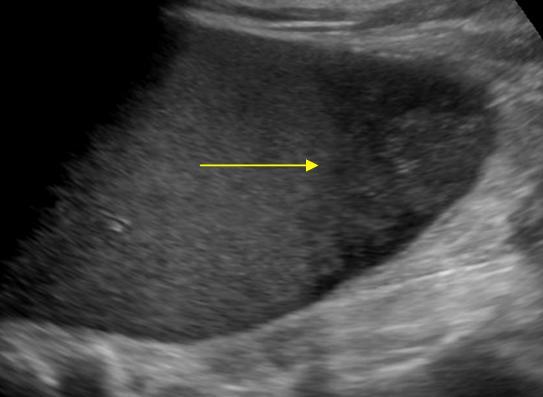

Nhồi máu lách

» Thông tin: Nam giới – 74 tuổi.

» Lâm sàng: Đau mạn sườn trái.